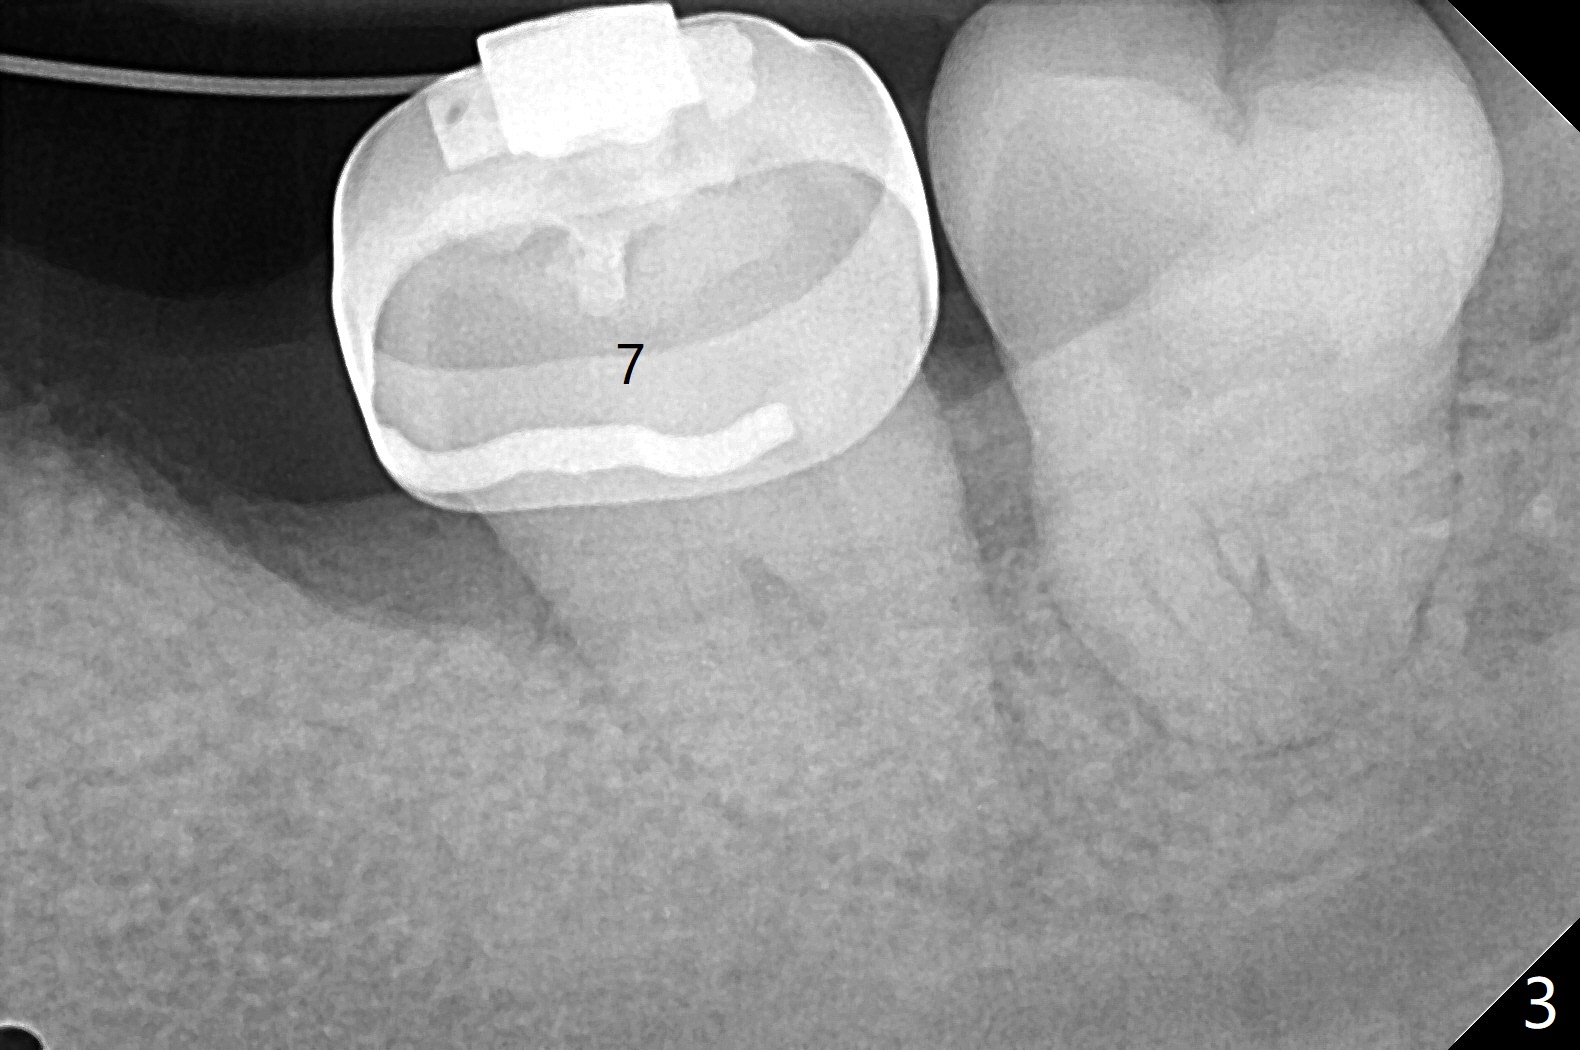

前几周介绍一个矫正砸锅病例,微型植体植入左上6(for intrusion,矫正压低)颊侧远中没有骨质区域,造成局部骨质缺损(图一:>)。颊侧,腭侧牙龈沟切口,翻瓣,清创后,植入粘性骨粉(图二:*,也在颊侧,腭侧植骨),覆盖PRF膜,使用4-0 Monoglyc缝线缝合。对于左下6缺失,原先病人(31岁女)要求前移7,8,初步矫正(2个月内)引起7松动(图三),经过讨论,病人同意拔除8,然后竖直7。拔出后,放置半块胶原塞(控制出血,图四:C),然后植骨(*),最后放置另外半块胶原塞(C),4-0 PGA缝合。术后一个月腭侧放置power chain压低磨牙(图五)。术后2.5个月缺牙间隙大于前磨牙,可以种植,同时7近中植骨(图六:*(粘性骨粉))。整合后利用6作为抛锚继续做7竖直。